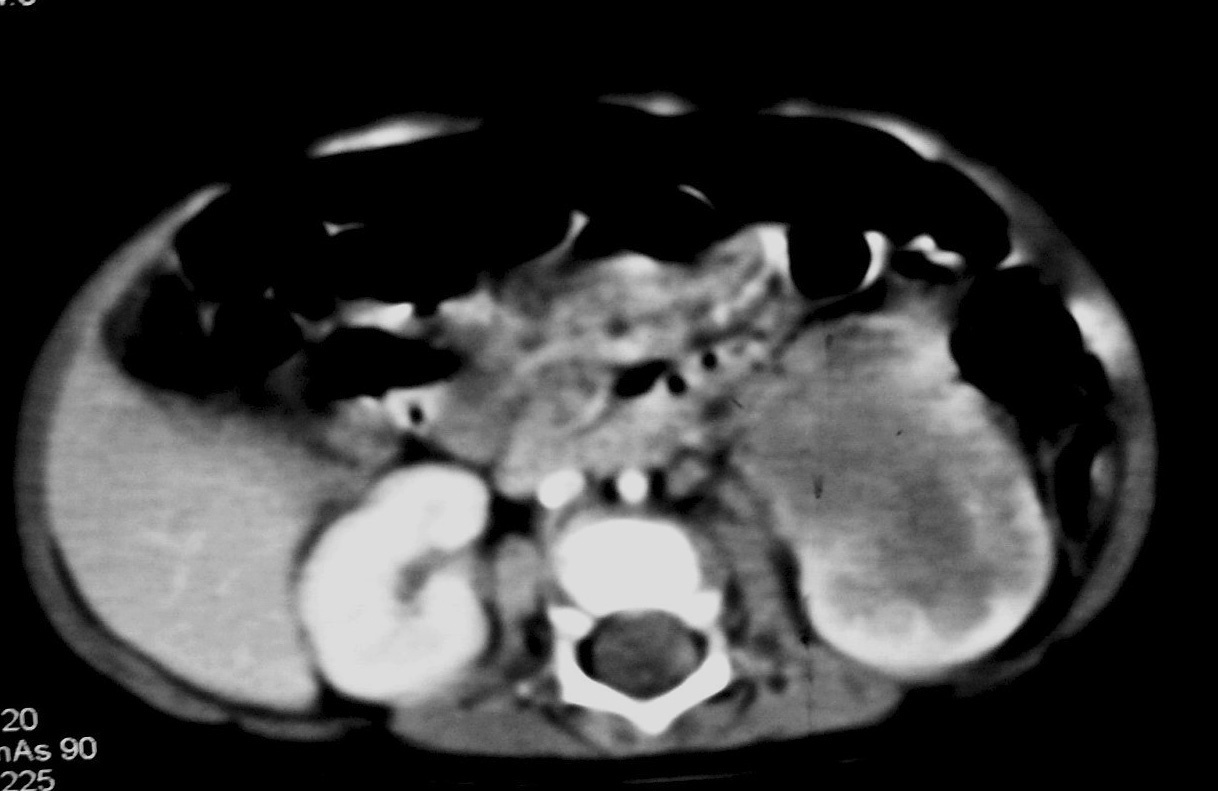

La única paciente con angiomiolipoma renal fue una niña de 10 años con esclerosis tuberosa. En el riñón derecho se identificó una tumoración en el polo superior, con gran crecimiento extrarrenal, densidad homogénea, mayor que la del parénquima renal y menor que la del hígado y relativamente ecogénica (fig. 9). No se constataron áreas grasas, tratándose de un angiomiolipoma con poco componente graso. En el riñón izquierdo se identificaron dos lesiones de pequeño tamaño con atenuación grasa compatibles con angiomiolipomas. Como hallazgos asociados se observaron en el hígado múltiples lesiones con contenido graso de características similares, compatibles con angiomiolipomas intrahepáticos.

Fig. 9. Angiomiolipoma. Niña con esclerosis tuberosa. (A) Ecografía abdominal. Corte renal derecho. Masa renal de ecogenicidad heterogénea y contornos lobulados. (B) Tomografía computarizada abdominal. Masa (M) en riñón derecho. No se identifica componente graso. En el hígado existen tres lesiones de atenuación grasa correspondientes a angiomiolipomas hepáticos (1, 2, 3).